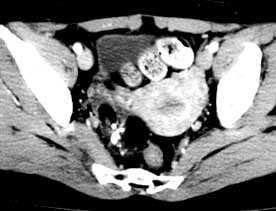

2.超聲診斷 良性囊性畸胎瘤的超聲所見常可分為以下幾種類型:

(1)類囊型:多為圓形或橢圓形囊壁較厚,多為單房,內為密集而反光強的光點,有時在內壁處可見一薄層液性區。

(2)囊內麵團征:囊內出現一個或數個反光強的光團,多為圓形,也有不規則光塊,可黏貼於內壁,光團後方無回聲。

(3)囊內發團征:囊內可見一圓形光團,其上方呈月牙形反光強的回聲,其後方衰減並伴明顯聲影(為脂類物團塊包裹一團毛髮構成)。

(4)囊內脂液分層征:上層為反光強密集光點回聲,此為一層脂類物;下層常為清亮液,有時亦可見液內漂浮少量光點兩層之間為脂液分層平面,較大的囊腫其液平面可隨體位變動而變化。

(5)複雜型:囊內結構複雜,可有光點脂液分層、強光團、發團征及麵團征等。